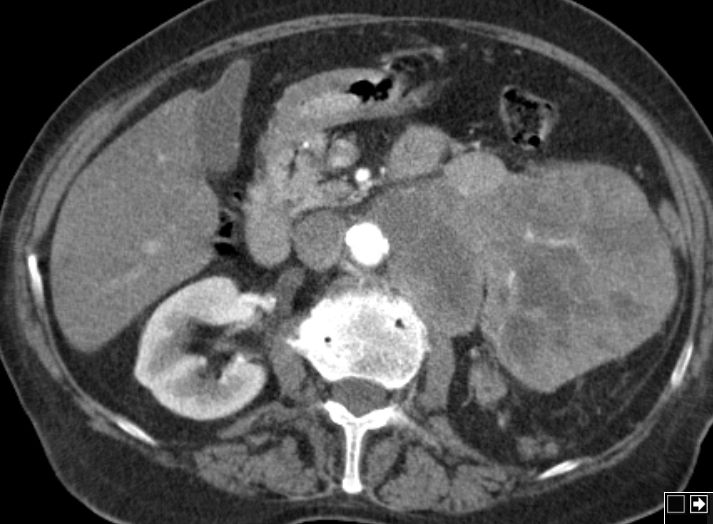

Nierenbecken-Karzinom in einer Doppelniere

Doppelniere links. Im oberen Anteil Hydroureter und Hydropyelons mit Wucherungen eines schlecht differenzierten Urothelkarzinoms mit Plattenepithelmetaplasie, infiltriert das umgebende Fettgewebe.G3. pT3, pN3 (2/3, 1 Lymphknoten mehr als 5 cm) L1. V0. Das CT zeigt den Nierenbeckentumor und eine Lymphknotenmetastase medial des erweiterten Ureters.